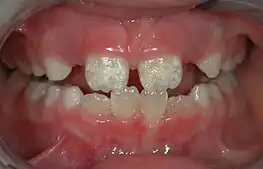

Some groups have spoken out against fluoridated drinking water, for reasons such as the neurotoxicity of fluoride or the damage fluoride can do as fluorosis. Fluorosis is a condition resulting from the overexposure to fluoride, especially between the ages of 6 months and 5 years, and appears as mottled enamel.[3] Consequently, the teeth look unsightly, although the incidence of dental decay in those teeth is very small. Where fluoride is found naturally in high concentrations, filters are often used to decrease the amount of fluoride in water. For this reason, codes have been developed by dental professionals to limit the amount of fluoride a person should take.[36] These codes are supported by the American Dental Association and the American Academy of Pediatric Dentistry.

Fluorosis leads to mottled enamel and occurs from overexposure to fluoride.[25]